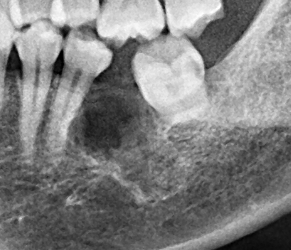

為了健保患者拔智齒的安全,遠離唇麻、舌麻、口鼻竇炎、大出血...等併發症,

☆本院特別巨資增設 ”千萬級3D AI透視電腦斷層”,並配合“成骨膠原蛋白”施作 (上述兩項目前健保無給付),讓您遠離神經傷害、口鼻竇(炎)相通...等併發症,除健保之外,難免會有避免併發症風險的自費項目,網路上經常會有看到智齒拔完後唇麻、舌麻、口鼻竇相通等併發症,在本院嚴格自我要求下,此類併發症在本院幾乎趨近於零。

(兩條紅線中間黑色區域即為神經管)

外面拔完時常術後唇麻舌麻,本院發生趨近於零